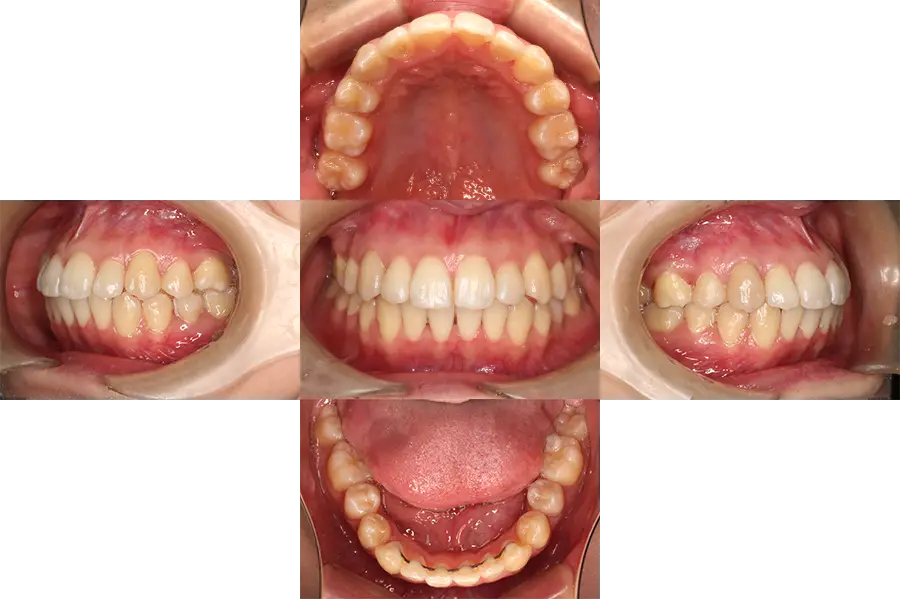

治療期間は約3年かかりましたが、口元を大きく改善でき、歯並びや咬み合わせもしっかり治すことができました。

現在、治療後約7年経過しておりますが後戻りなく安定しております。